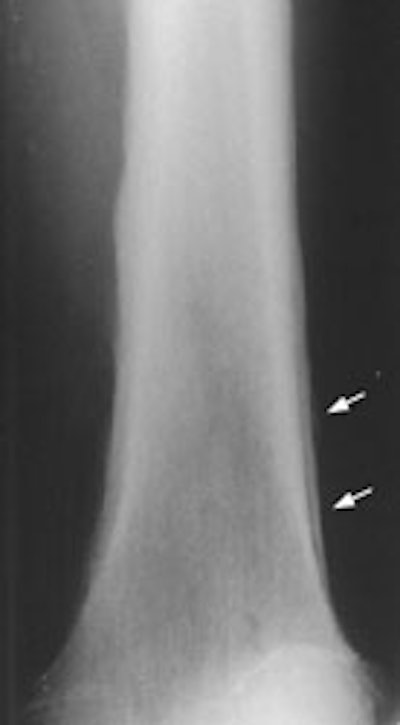

Example 2: This is an interesting case of a patient with non-small-cell lung cancer who complained of right shoulder pain. The bone scan demonstrates a bone lesion in the proximal right humerus (blue arrow) consistent with a metastasis. The scan also revealed linear uptake of tracer along the distal femurs and tibias bilaterally (black arrows). Uptake in the forearms was more irregular. A coned down plain film of the distal left femur demonstrated a solid periosteal reaction (white arrows). The findings are consistent with hypertrophic osteoarthropathy- a paraneoplastic condition seen in association with bronchogenic carcinoma.

NOTE:  Click directly on the image to enlarge.